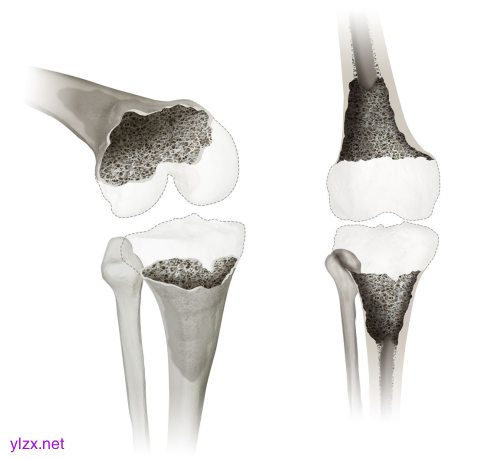

显示膝关节缺陷分类(KDC)的4型缺陷。类型4描述了该分类中影响股骨和/或胫骨骨干的最严重的骨丢失。提供了3D斜视图(左)和正视图(右)